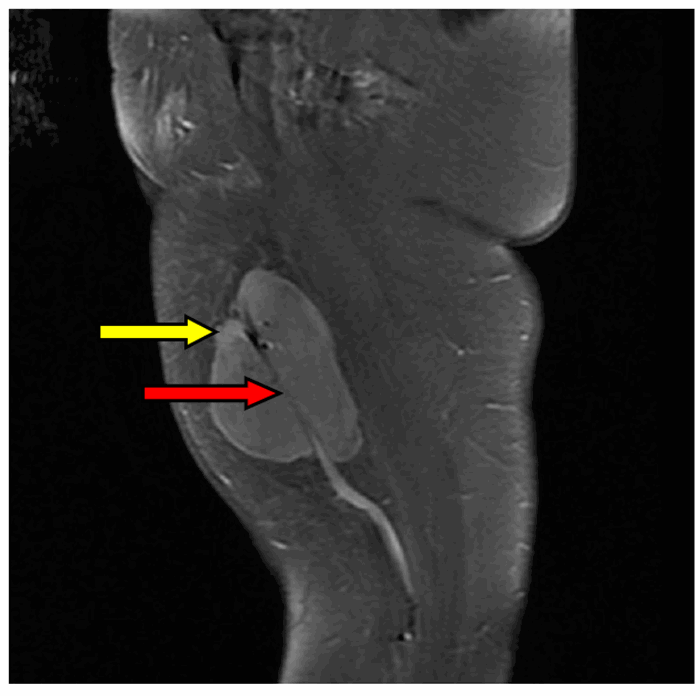

- RM: es la técnica de elección para evaluar la extensión local. Muestra una masa heterogénea, con áreas de necrosis y hemorragia (señal hiperintensa en T2, áreas de necrosis sin realce), y permite valorar la relación con los paquetes vasculonerviosos.

Hallazgo radiológico característico